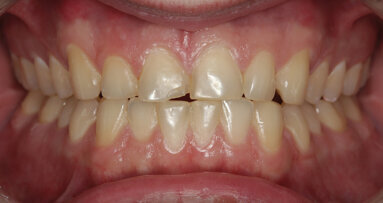

A 40-year-old female patient presented to our dental surgery with an irreparable tooth #21 (Fig. 1). The periapical radiograph revealed an approximately 7 mm periapical translucency with widening of the periodontal ligament in the upper third of the root (Fig. 2). Owing to the clinical conditions (high smile line and good oral hygiene), we decided to use a two-piece ceramic implant, ZERAMEX XT (Dentalpoint).

Fig. 1: Initial clinical situation.